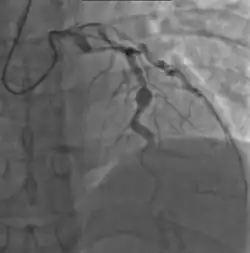

- Angiography was historically used to detect coronary artery aneurysms, and remains the gold standard for their detection, but is rarely used today unless coronary artery aneurysms have already been detected by echocardiography.

Heart complications are the most important aspect of Kawasaki disease, which is the leading cause of heart disease acquired in childhood in the United States and Japan.[32] In developed nations, it appears to have replaced acute rheumatic fever as the most common cause of acquired heart disease in children.[16] Coronary artery aneurysms occur as a sequela of the vasculitis in 20–25% of untreated children.[53] It is first detected at a mean of 10 days of illness and the peak frequency of coronary artery dilation or aneurysms occurs within four weeks of onset.[49] Aneurysms are classified into small (internal diameter of vessel wall <5 mm), medium (diameter ranging from 5–8 mm), and giant (diameter > 8 mm).[32] Saccular and fusiform aneurysms usually develop between 18 and 25 days after the onset of illness.[16]

Many risk factors predicting coronary artery aneurysms have been identified,[22] including persistent fever after IVIG therapy,[57][58] low hemoglobin concentrations, low albumin concentrations, high white-blood-cell count, high band count, high CRP concentrations, male sex, and age less than one year.[59] Coronary artery lesions resulting from Kawasaki disease change dynamically with time.[4] Resolution one to two years after the onset of the disease has been observed in half of vessels with coronary aneurysms.[60][61] Narrowing of the coronary artery, which occurs as a result of the healing process of the vessel wall, often leads to significant obstruction of the blood vessel and the heart not receiving enough blood and oxygen.[60] This can eventually lead to heart muscle tissue death, i.e., myocardial infarction (MI).[60]